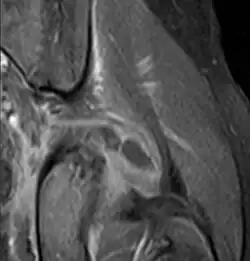

| Transverse T2 magnetic resonance imaging section through the hip region showing abscess collection in a patient with pyomyositis. | |

Axial T1 weighted fat suppressed post IV gadolinium contrast enhanced MRI image showing a mutliloculated bacterial abscess in the left gluteal muscle which grew Staphylococcus aureus (methicillin sensitive) thought to be due to tropical pyomyositis.

Coronal fat suppressed post contrast image showing a multiloculated bacterial abscess in the left gluteus minimus muscle due to tropical pyomyositis.